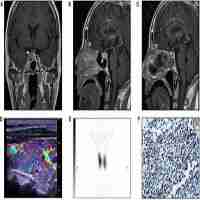

| Abstract | Background Graves’ disease is the commonest cause of thyrotoxicosis whilst thyrotropin (TSH)-producing pituitary adenomas (thyrotropinomas, TSHomas) are very rare and account for just 1–2% of all pituitary adenomas. Coexistence of a TSHoma and Graves’ disease has been very rarely reported. Here, we report a case of a patient whose initial presentation with primary thyrotoxicosis due to Graves’ disease, was subsequently followed by a relapse of thyrotoxicosis due to a probable TSHoma. Case A sixty-eight year old woman was referred to our department with classical features of thyrotoxicosis. Initial biochemistry confirmed hyperthyroxinaemia [free thyroxine (fT4) 20.4 pmol/L (reference range 7.0–16.0)] and a suppressed TSH [< 0.02mIU/L (0.50–4.20)]. A technetium pertechnetate uptake scan was consistent with Graves’ Disease. She was treated with carbimazole for 18 months and remained clinically and biochemically euthyroid. After stopping carbimazole her fT4 started to rise but TSH remained normal. Laboratory assay interference was excluded. A TRH stimulation test demonstrated a flat TSH response and pituitary MRI revealed a microadenoma. Remaining pituitary hormones were in the normal range other than a slightly raised IGF-1. An 11C-methionine PET/CT scan coregistered with volumetric MRI (Met-PET-MRICR) demonstrated high tracer uptake in the left lateral sella region suggestive of a functioning adenoma. The patient declined surgery and was unable to tolerate cabergoline or octreotide. Thereafter, she has elected to pursue a conservative approach with periodic surveillance. Conclusion This is a very unusual case of thyrotoxicosis caused by two different processes occurring in the same patient. It highlights the importance of considering dual pathology when previously concordant thyroid function tests become discordant. It also highlights a potential role of Met-PET-MRICR in the localisation of functioning pituitary tumours. |